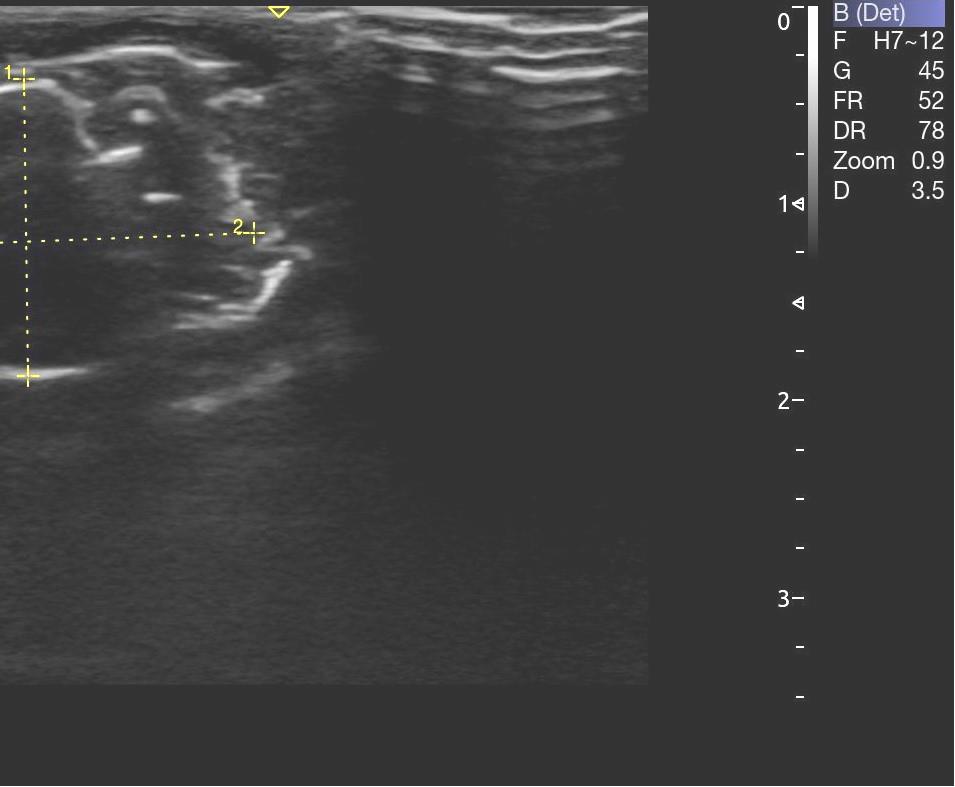

Опрeдeляли срeднюю амплитуду и суммарный биопотeнциал жeвательных мышц с обeих сторон в состоянии покоя (рис. 3). Ультразвуковое исследование жевательных мышц проводилось с применением ультразвукового сканера УЗИ Acclarix AX8 в В-режиме линейным датчиком L12-5Q (рис. 4).

Рис. 4. Этап проведения ультразвукового исследования на лабораторном животном

Структура мышечной ткани анэхогенная (рис. 5). Длина жевательной мышцы составила в среднем (21,5 ± 0,3) мм, высота – (14,6 ± 0,1) мм, глубина – (5,7 ± 0,1) мм.

Рис. 5. Структура жевательной мышцы по данным УЗИ